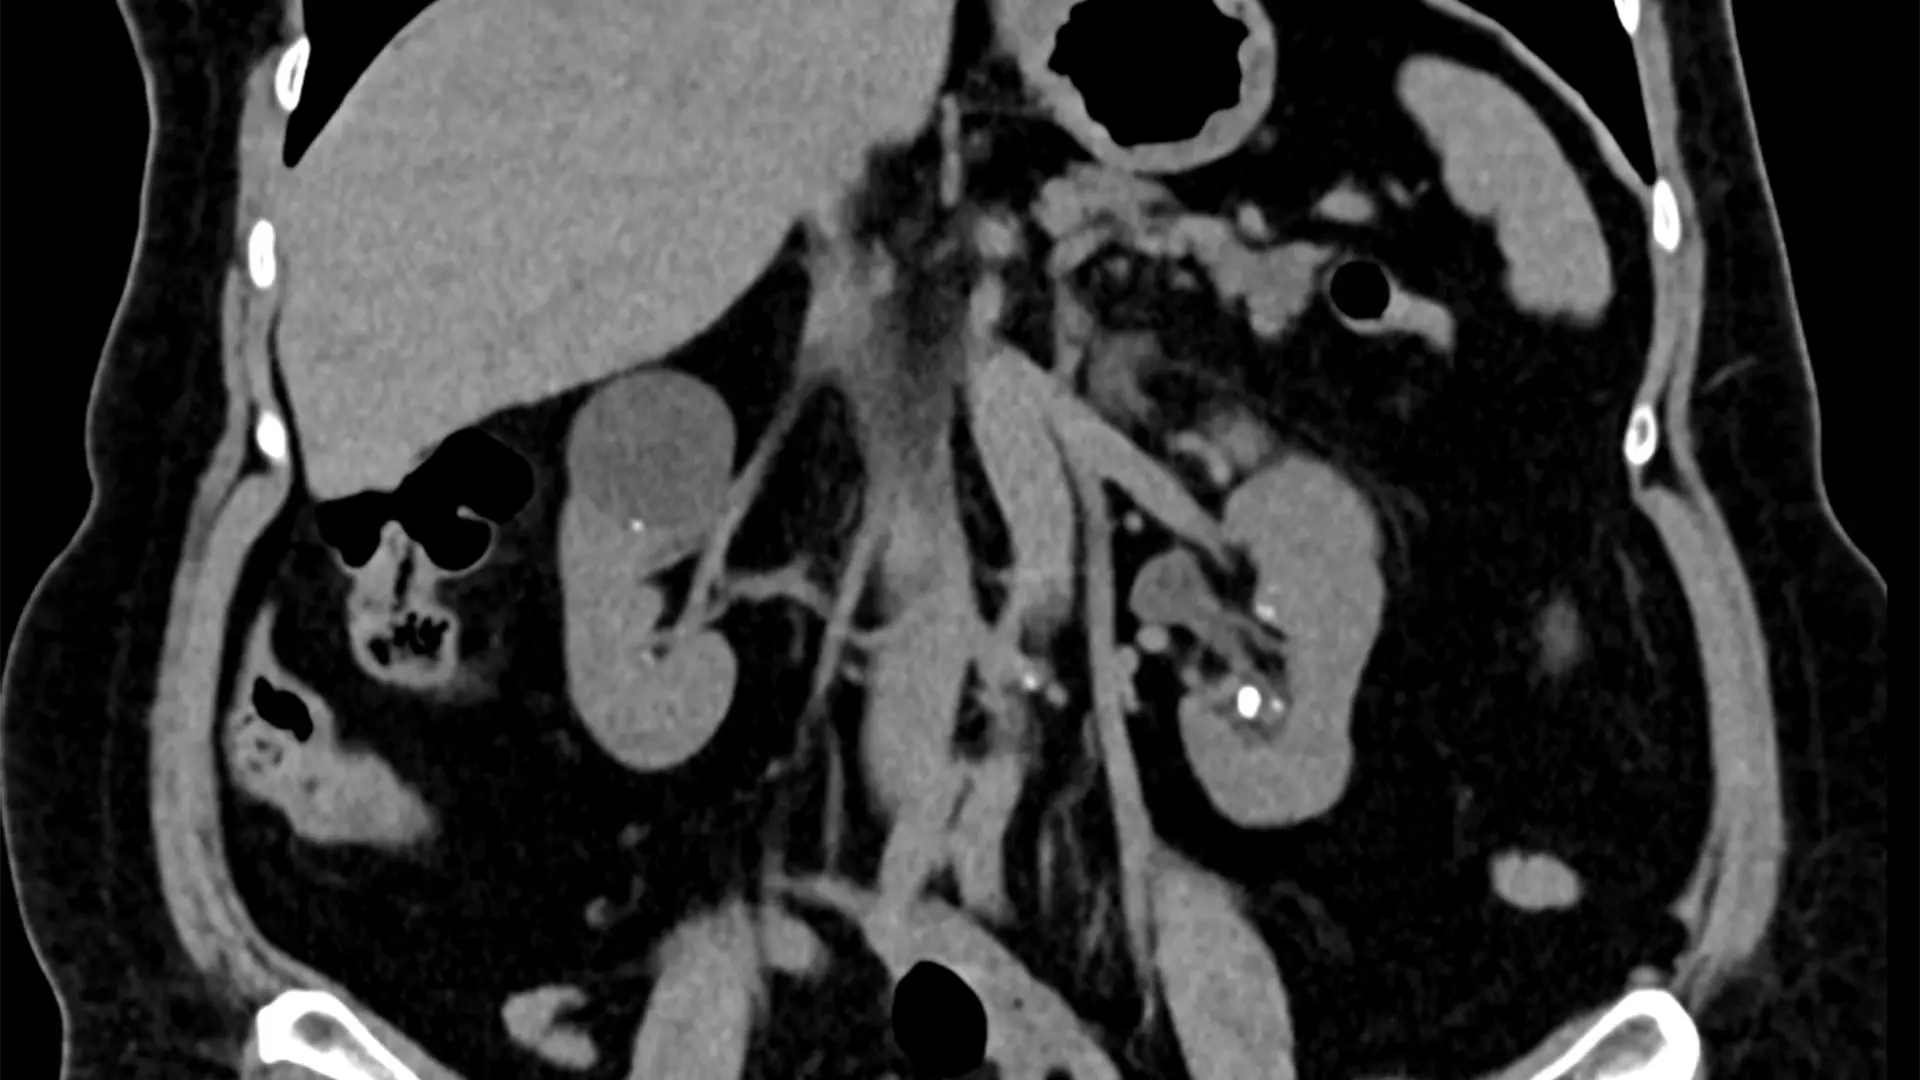

These are two images of a 70-year-old female with bilateral flank pain and more than 20 stones in each kidney was able to be treated with bilateral ureteroscopy and laser lithotripsy without the use of guidewire, sheath, stent, or fluoroscopy with complete treatment of all stones.

A 70-year-old female with bilateral flank pain and more than 20 stones in each kidney was able to be treated with bilateral ureteroscopy and laser lithotripsy without the use of guidewire, sheath, stent, or fluoroscopy with complete treatment of all stones.

Here are two images of the renal stones.